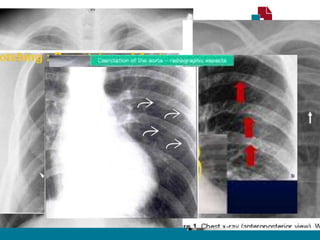

RADIOGRAFIA TORÁCICA

• Sinal de Roesler:

• Erosões bilaterais na borda inferior dos arcos costais (3ª - 9ª).

• Sinal do “ 3 invertido”

• Dilatação Subclávia E.

• Segmento estenótico aparece como um entalhe

• Dilatação pós estenótica.

• Contorno do arco aórtico apagado.